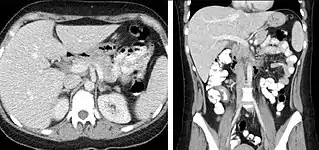

A CT scan image showing a ruptured abdominal aortic aneurysm.

FIGURE 3. Axial (left) and coronal (right) CT angiography images of the abdominal aorta evaluating for aortic aneurysm.

CT angiography (CTA) is highly effective for evaluation of the arterial system, and has largely replaced conventional angiography due to the lower risk profile and ability to survey the entire abdomen. Images are acquired after a rapid bolus of intravenous contrast material (3-7 cc/s) during the arterial phase (15–35 seconds after injection) when the concentration of contrast material in the arterial system is high (figures 3). Images are usually acquired using narrow collimation (<1 mm) and can be retrospectively reconstructed using dedicated 3-dimensional workstations and software. CTA is commonly used in the head and chest in the evaluation of pulmonary emboli, aneurysms, vascular malformations, dissection, bleeding and ischemia. Indications for early arterial phase imaging include: evaluation of aneurysms or dissections (cerebral, aortic, etc.), hepatic, splanchnic or renal arterial anatomy, and arterial imaging in liver or kidney transplantation. Single phase arterial imaging is often used in the evaluation of trauma patients either a complete chest/abdomen/pelvis examination with arterial phase imaging of the chest and portal venous phase imaging of the abdomen/pelvis or just a portal venous phase of abdomen and pelvis depending on the mechanism and severity of the trauma. CTA is also commonly performed in the abdomen and pelvis for evaluating vascular malformations and in the evaluation of bleeding. Mesenteric ischemia can also be evaluated using CT angiography. CTA of the abdomen and pelvis is often performed in combination with a CTA for evaluating the extremity vasculature.